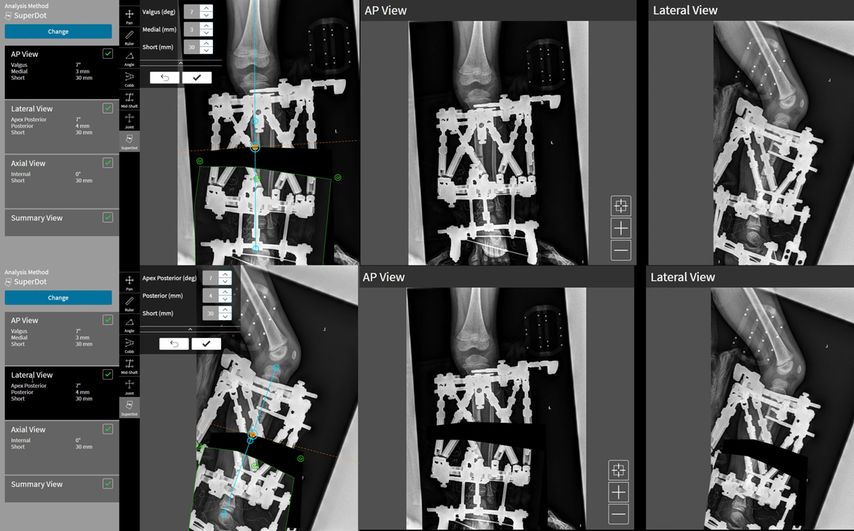

Die neue Software des TSF (SmartTSF) vereinfacht nun all diese Schritte. Hier werden nach Angabe der Lokalisation und Eingabe der verwendeten Hardware postoperative Röntgen in 2 Ebenen eingegeben. Diese müssen streng a.p. und seitlich durchgeführt werden und müssen ein Kalibrierungs- und 3D-Ortungstool (Beacon) mitabgebildet haben (Abb. 6). In der Software kann nun unter Verwendung des Workflows „SuperDot“ das Moving-Fragment ausgeschnitten und mit der Maus in die entsprechend korrigierte und/oder verlängerte Position gezogen werden (Abb. 7). Um die exakte anatomische Position/Korrektur zu finden, stehen Hilfslinien bereit, die die Planung bei diesem Schritt ermöglichen. Aus der gewählten Position entnimmt die Software automatisch die Deformitätenparameter. Es stehen auch noch der Workflow „TraumaDot“ für Frakturen und der Workflow „Origin & CP“ für sehr geübte klassische Anwender zur Verfügung.

Abb. 7: Bei der „SuperDot“-Planung kann das Moving-Fragment, in diesem Fall das distale Segment, einfach in die gewünschte Position gezogen und rotiert werden. Daraus werden die Deformity-Parameter automatisch kalkuliert. Das Prä- und das Post-Korrektur-Bild werden für beide Ebenen simuliert